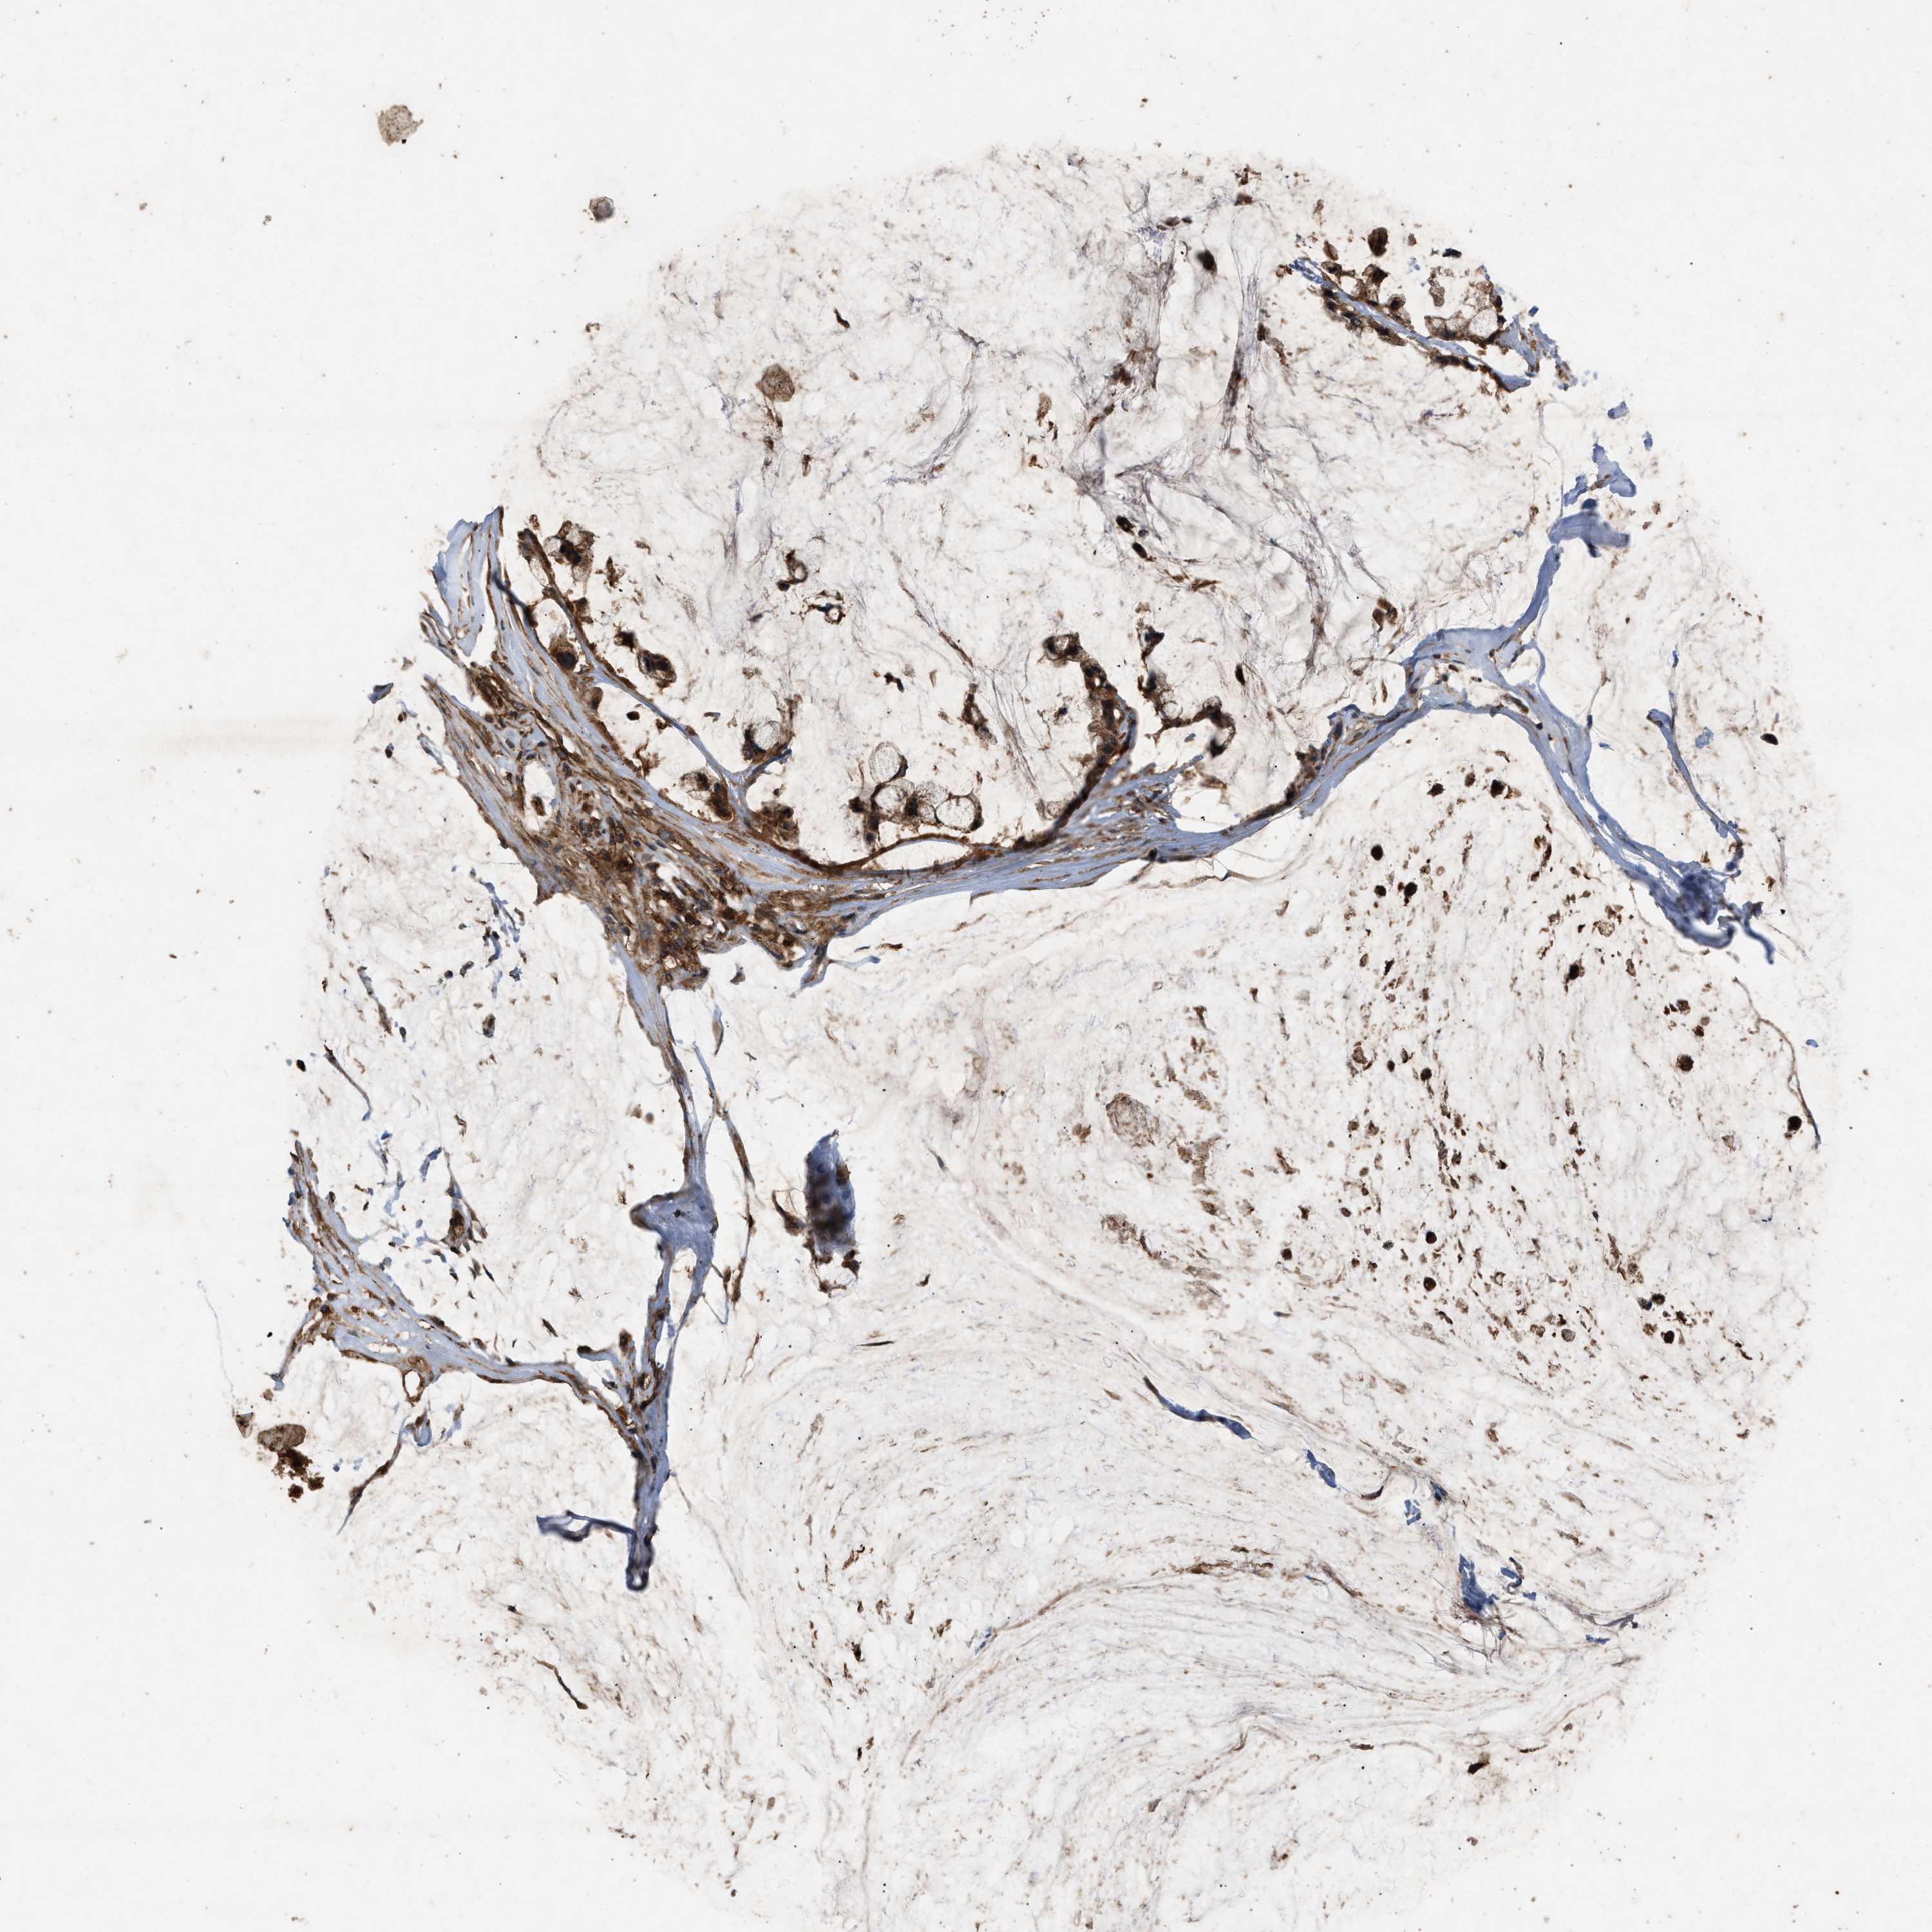

OVARIAN CANCER - Protein expressioni

A mouse-over function shows sample information and annotation data. Click on an image to view it in a full screen mode. Samples can be filtered based on level of antibody staining by selecting one or several of the following categories: high, medium, low and not detected. The assay and annotation is described here.

Note that samples used for immunohistochemistry by the Human Protein Atlas do not correspond to samples in the TCGA dataset.

Antibody stainingi

Antibody staining in the annotated cell types in the current human tissue is reported as not detected, low, medium, or high, based on conventional immunohistochemistry profiling in selected tissues. This score is based on the combination of the staining intensity and fraction of stained cells.

Each image is clickable and will lead to virtual microscopy that enables deeper exploration of all samples and also displays staining intensity scores, fraction scores and subcellular localization as well as patient and tissue information for each sample.

Antibody HPA040736

Cystadenocarcinoma, serous, NOS